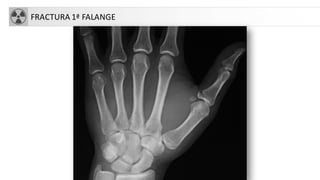

FX FALANGES

• Fx extremo distal última falange (+frecuente). Asocia a

hematoma subungueal

• Fx base falange distal: avulsión

• Avulsión dorsal: puede asociarse a territorio inserción del

extensor: dedo en martillo

FX FALANGES 1 DEDO

FRACTURA 1ª FALANGE